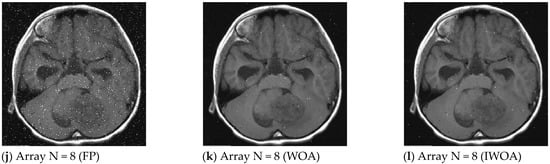

The image enhancement effect based on the array model method is shown in Figure 9. It can be seen from Figure 9 that with the increase of array unit size, the noise black and white spots on the restored image of the fixed parameter array model method, the parameter adaptive array model method based on WOA and the parameter adaptive array model method based on IWOA proposed in this paper become less and less, and the restored image gradually becomes clearer. Among them, under different array unit sizes, the restored images obtained by the parameter adaptive array model method based on IWOA proposed in this paper are the clearest. When the array unit size is 8, the restored image obtained by the IWOA-based parameter adaptive array model method proposed in this paper is very similar to the original image, with only a few noise points.

Figure 9.

Comparison of denoising effect of MRI image.

The comparison results of PSNR of the above three methods are shown in Table 6. As can be seen from Table 6, when the number of arrays is 1, the PSNR value obtained by the three model methods for image restoration is relatively small, and the processing effect is not good. With the increase of the size of the array element, the PSNR of the restored image of the three model methods also increases, so that the image restoration effect is better. Moreover, the PSNR value of the restored image of the IWOA-based parameter adaptive array model method proposed in this paper is the largest, and the image enhancement effect is the best. Experimental results show that the proposed IWOA-based parametric adaptive array model method has significant advantages in image enhancement.